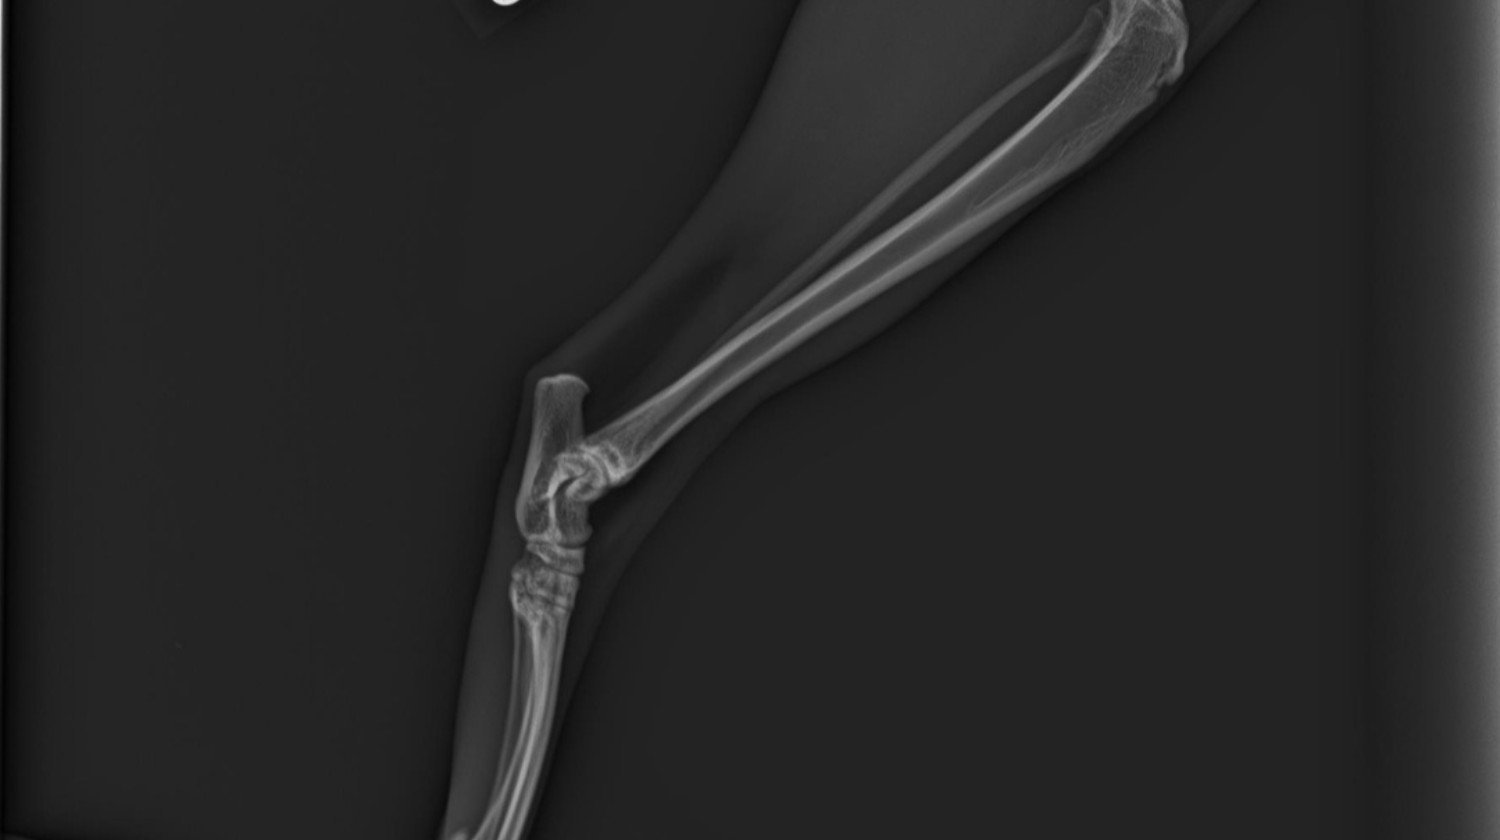

Notre famille vient de vivre une tragédie déchirante : notre chat bien-aimé a été renversé par une voiture. Sa patte est gravement cassée, elle souffre énormément et les vétérinaires disent que seule une intervention chirurgicale immédiate et salvatrice peut lui donner une chance de survivre. Chaque minute d'attente diminue ses chances.

Une immense tragédie est arrivée à notre famille : notre chat adoré a été renversé par une voiture. Dans l'accident, sa patte a été gravement cassée, il souffre énormément, et les vétérinaires disent que seule une chirurgie immédiate et salvatrice peut lui donner une chance de survie. Chaque minute d'attente diminue ses chances de survie.